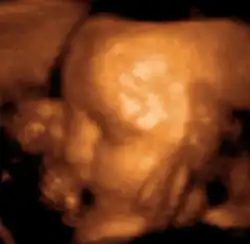

Ecografía 3D y 4D

En los últimos tiempos se ha podido ver una revolución en el campo de la medicina materno-fetal. Esa revolución, además, no solo ha afectado a la medicina en sí misma, sino que ha aportado a la sociedad la posibilidad de establecer una unión emocional con los neonatos mucho más profunda de lo que hasta ahora se creía posible, gracias a una calidad de imagen que permite ver el aspecto del futuro bebé en fotografía (3D) o en imagen en movimiento (4D).

Para lograrlo, mediante el ecógrafo, se emiten los ultrasonidos en cuatro ángulos y direcciones, pasando el emisor suavemente por la barriga del paciente, a la cual se le ha aplicado previamente un gel para mejorar la eficiencia del proceso. Los ultrasonidos rebotan y son captados por el ordenador, que procesa automáticamente la información para reproducir en la pantalla la imagen a tiempo real del bebé.